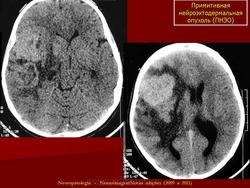

ГМ. Примитивная нейроэктодермальная опухоль (ПНЭО). +

Примитивная нейроэктодермальная опухоль (ПНЭО)